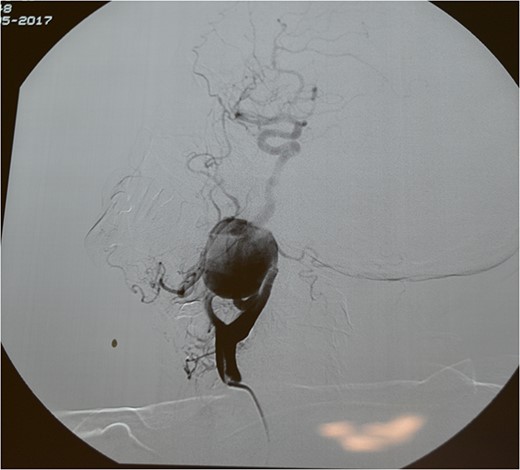

A 71-year-old woman was referred to the vascular surgery department of our hospital with an asymptomatic, pulsative, submandibular mass that she had noticed in the right side of her neck for a month and with ‘potato voice’. Her medical history was non-contributory. MRI, 3D-CT (Fig. 1) and conventional angiography (Fig. 2) revealed an aneurysm of the right ICA. The aneurysm was located in the upper third of the artery and its maximal diameter was more than 4 cm, lining to the right parapharyngeal space, whereas the aerodigestive track was limited and dislocated in the height of the aneurysm.

Computed tomography angiography of the carotids with 3D reconstruction.